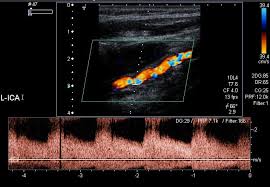

경동맥 초음파는 혈관 벽과 혈류를 실시간 영상으로 관찰할 수 있어 여러 질환을 조기에 파악하는 데 유용합니다. 확인 가능한 대표 적인 경동맥 초음파 검사로 알수있는병은 다음과 같습니다.

- 경동맥 협착증(혈관이 좁아진 상태)

- 동맥경화증(죽상경화로 혈관벽 두꺼워짐)

- 혈관 플라크(지방, 콜레스테롤 침착물)

플라크가 혈류에 영향을 줄 정도로 커지면 협착이 발생하고, 이 플라크 조각이 떨어져 나가 뇌혈관을 막으면 뇌경색이 발생할 수 있기에 조기 발견이 매우 중요합니다. 또한 IMT(혈관 내막-중막 두께) 수치가 정상보다 두꺼워진다면 심혈관 질환의 발병 가능성이 높은 것으로 평가됩니다. 즉, 경동맥 초음파 결과는 뇌뿐 아니라 심장 건강 상태를 간접적으로 나타내는 지표로도 활용됩니다. 특히 다음과 같은 상황에서 더 세밀한 해석과 대처가 필요합니다.

- 협착률 50% 이상: 증상이 없어도 위험군으로 관리 필요

- 협착률 70% 이상: 뇌졸중 발생 위험 매우 높아 치료 고려

- 불안정 플라크: 껍질이 얇아 쉽게 파열될 수 있어 고위험군

- 혈류 속도 측정과 플라크 유무 확인

- 혈류 속도 증가 여부